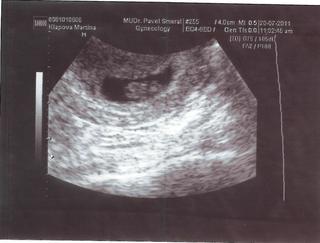

@saronka paráda, gratuluju 🙂 🙂 Když je to takhle krásně vidět ještě před ms, tak to mimoň určitě není. Teď jen myslet pozitivně a neděsit se samého píchání a pobolívání. To jsou jen srůsty po tom chybějícím vejcovodu. Všechno bude v pohodě a budeš se moct těšit na jarní miminko 2012 🙂 Ještě jednou moc gratuluju.

ahoj holky..tak hlásím // na testu 🙂) bolel mě levý vaječník takže tam kde není vejcovod..zatím jen hcg 137, a 22.8. jdu na ultz. pro jistotu jdu 8.8. na kontrolní HCG. jinak ale dle testů slabá čárka v litmitu 8DPO 🙂 mimoň 17DPO jen pidi stíneček 🙂)